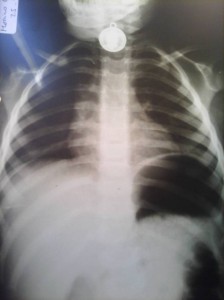

Alerta niños: cómo actuar ante la ingesta de cuerpos extraños

Suele decirse que los accidentes más graves ocurren en el hogar. Es el caso de anillos, agujas, medallas y hasta pilas que pueden ser aspirados o tragados por los niños y provocar muerte por obstrucción o problemas...